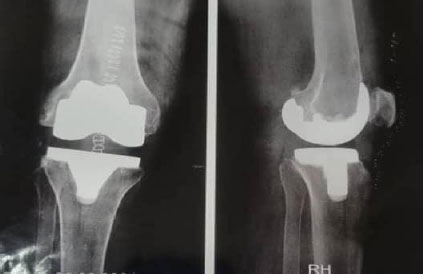

Standard anteroposterior and lateral radiographs were used to verify the proper positioning of femoral and tibial components (Fig. 5). However, a postoperative pangonogram, which would have allowed precise measurement of the mechanical axis (HKA), was not routinely performed due to its limited availability and high cost in our setting. This represents a limitation in the accurate evaluation of axial corrections in this study.

Regarding implant positioning, in our series:

- 21 knees (72.4%) showed a femoral component perpendicular to the mechanical axis with a mean α angle of 90° ± 4°; (Fig. 6)

- 18 knees (62.1%) had a tibial component perpendicular to the mechanical axis (β angle = 89° ± 8°);

- On the sagittal plane, 17 knees (58.6%) presented a well-aligned femoral component (γ angle = 0° ± 2°) and 16 knees (55.2%) a physiological tibial slope (δ angle = 0° ± 2°).

- The patella was centered in all knees, reflecting good patellar tracking and balance.

Postoperative anteroposterior and lateral radiographs showing proper positioning of the prosthesis in a patient operated on for primary knee osteoarthritis.

Postoperative radiograph showing a right total knee arthroplasty with the femoral component positioned perpendicular to the mechanical axis, corresponding to a mean α angle of 90° ± 4°.